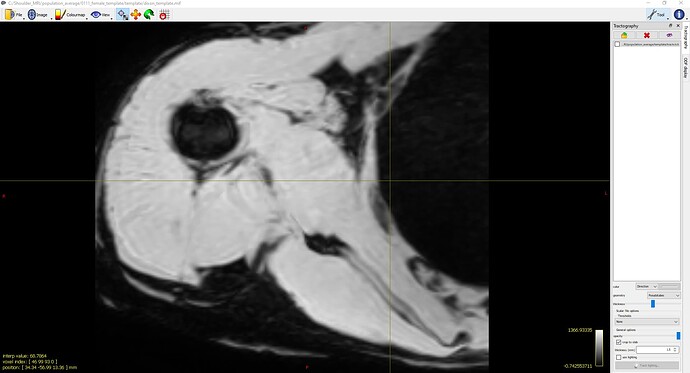

However, the issue arises after the non-linear registration step. I’ve experimented with two different sets of settings for non-linear registration (the mask input contains segmentations for all four rotator cuff muscles):

- Settings A:

population_template ../template/fod_inout/ ../template/fod_template.mif ../template/dixon_input/ ../template/dixon_template.mif -mask_dir ../template/mask_input/ -template_mask ../template/mask_template.mif -voxel_size 0.75 -nl_metric_radius 3 -nl_disp_smooth 0.75 -nl_update_smooth 1 -nl_niter 50,50,50,50,50,50,50,50,50,50,50,50,50,50,50,50(See Screenshot 2)